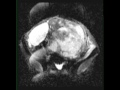

19-year-old female with a history of neurofibromatosis type I. The patient presented with abdominopelvic pain. Centered low within the abdomen and extending into the pelvis, there is a large solid and cystic lesion with well circumscribed margins and lobular components that are T2/STIR hyperintense and T1-iso- to hypointense. There are several nodular components of the lesion which demonstrate diffusion restriction and very minimal enhancement. There is an additional lesion centered within the left femoral neck region. Following percutaneous biopsy, a diagnosis of Triton tumor was made. Triton tumors represent a form of malignant peripheral nerve sheath differentiation with skeletal muscle differentiation. This subtype accounts for approximately 5% of malignant peripheral nerve sheath tumors and are associated with poorer outcomes than conventional malignant peripheral nerve sheath tumors. Malignant peripheral nerve sheath tumors can develop anywhere in the body but usually along the major nerve roots. Primary tumors most commonly occur in the extremities followed by the trunk and the head and neck region. Tumors in the extremities have better outcomes compared with other sites.